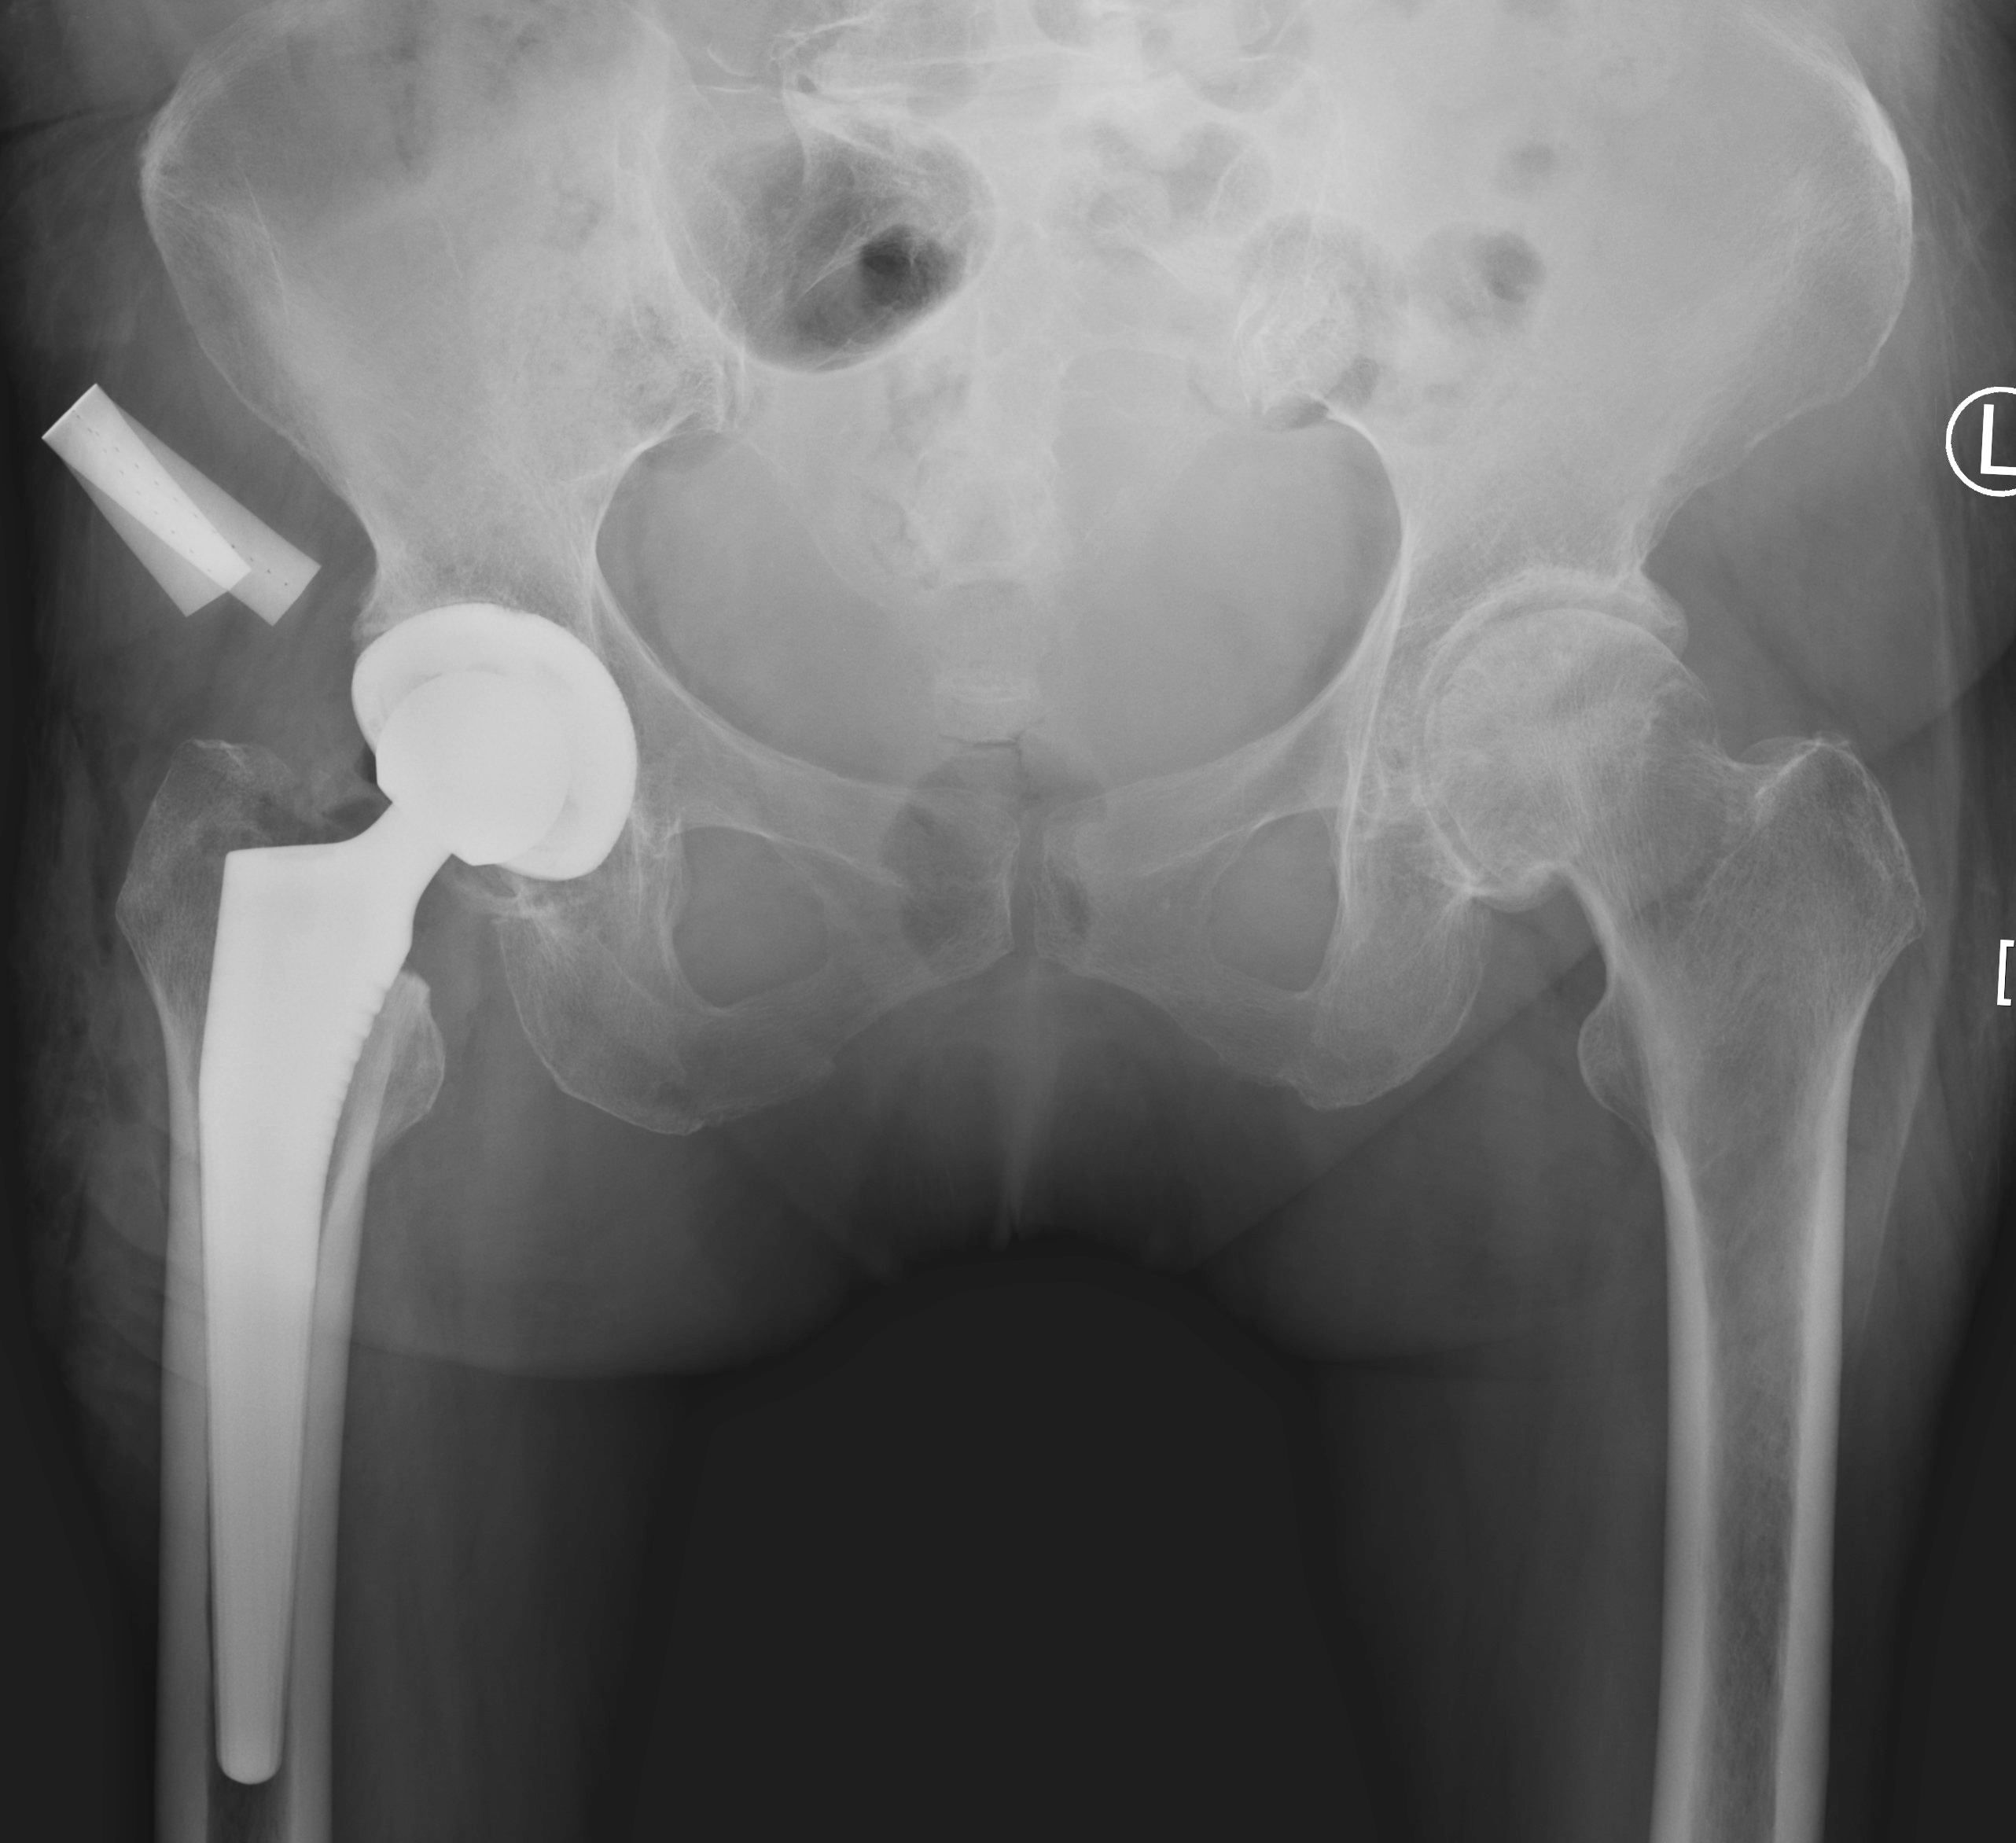

该患者为一名68岁女性,患髋关节骨性关节炎多年(图1),常年的疼痛和活动受限严重影响了患者的生活质量。在术中,手持导航系统可以显示髋臼磨挫和髋臼杯假体的安放角度,并显示髋关节的偏心距以及下肢长度的重建情况。手持导航仪上的实时反馈数据,可以将假体安放的位置和角度精确到1毫米和1度,从而最大程度地避免了人工操作的误差。在此导航系统的辅助下,患者的假体被安放到了准确的位置,下肢长度和偏心距得到了重建,并获得了非常满意的髋关节活动度和稳定性。手术仅用时60余分钟,与传统导航相比缩短了手术时间。患者术后的影像学结果显示,假体的位置、角度和肢体长度都非常理想(图2)。手术当天晚上患者即可下地活动,住院仅2天后,患者即平稳出院回家。

图1. 患者术前X光片。女性,68岁,双侧髋关节骨性关节炎。

图2. 患者术后X光片。假体位置和角度理想,下肢偏心距和长度得到了重建